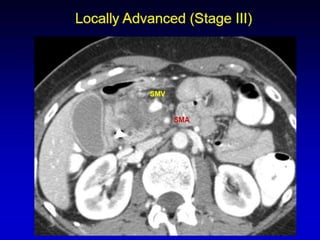

CT

 “Pancreatic protocol CT” is the gold

standard of investigation to stage the

disease and assess the operability

 Triple phase CT

 Closer cuts

 Water used as an intraluminal contrast

 Helical or multislice

 Focal or diffuse mass lesion which is hypo

dense (low attenuation) and hypo vascular

(poor contrast enhancement)

 Dilated MPD and CBD